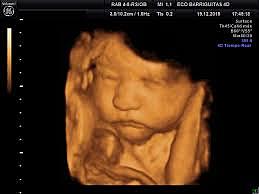

-The 4D

The 14 of agost de 2015